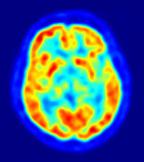

Los cambios se ven con resonancias

La exposición fetal al alcohol afecta a la estructura del cerebro de los niños

Los niños que han estado expuestos al alcohol durante el desarrollo fetal presentan cambios en la estructura cerebral y el metabolismo, visibles mediante diversas técnicas de imagen, según un nuevo estudio presentado en la reunión anual de la Sociedad Radiológica de Norteamérica (RSNA, en sus siglas en inglés).